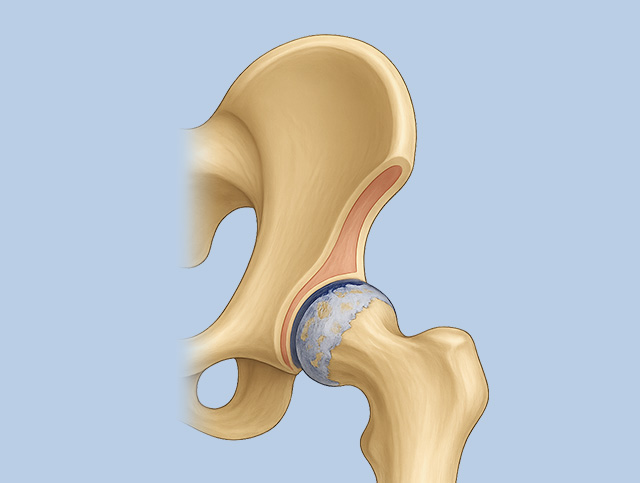

허벅지뼈의 둥근 머리와 골반의 움푹 들어간 고관절 연결 부위가 부딪히면서 염증, 통증 발생

골반 앞쪽이나 사타구니 쪽 통증, 다리를 돌리거나 양반다리 하기 어려워짐. 악화되면 허벅지, 엉덩이, 허리까지 통증 확산

정상 고관절 / 관절염을 동반한 고관절

퇴행성 고관절염

고관절에 염증이 발생하여 통증, 절뚝거림, 고관절 움직임 제약

고관절 연골 두께 감소, 활액막 두꺼워짐, 물이 차는 증상 등 발생